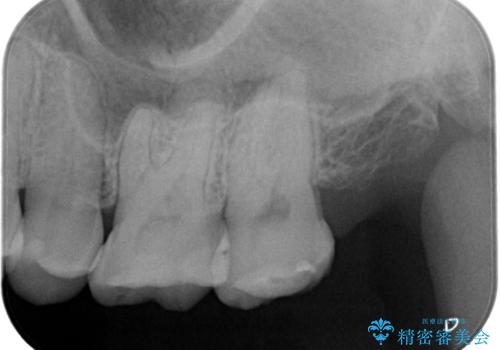

【セラミックインレー】適合の良いセラミックインレーを入れたい。

- 毎回フロスが引っかかることを気にされており、改善のため適合の良いセラミックインレーで修復しました。

以前に他院で詰め物をいれた時は、フロスが毎回ちぎれて大変だったそうですが改善して喜んでおられました。